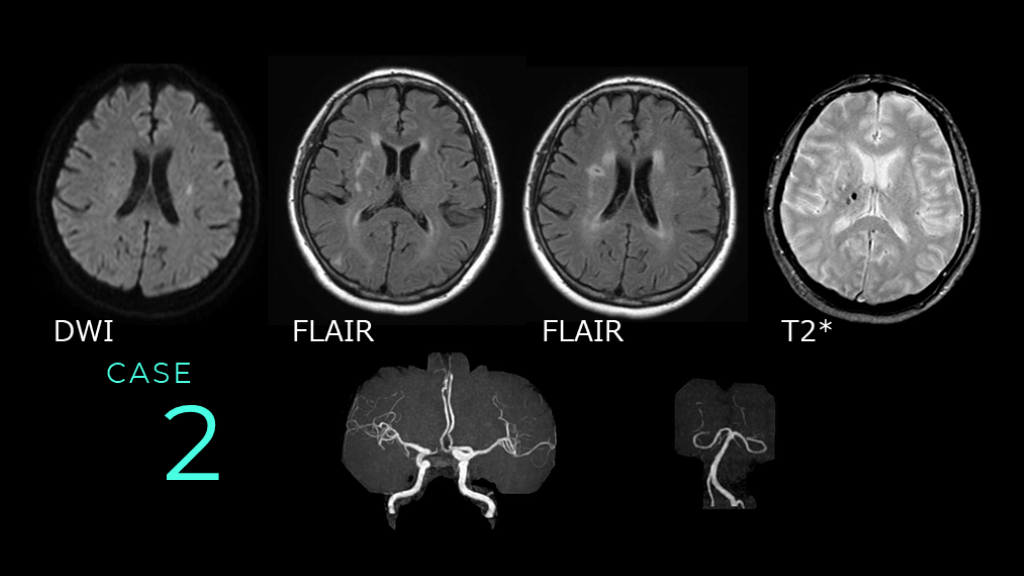

2 CASE DWI FLAIR FLAIR T2*

2 CASE DWIで放線冠レベルのスライスで 淡い高信号の白質病変を認める。 DWI

CASE 2 DWIで指摘された病変はFLAIRでは目立たない。 FLAIRでは、脳室周囲の白質に高信号病変が散在している。 FLAIR      FLAIR

2 CASE T2*では、右側大脳の基底核レベルのスライスに、microbleedsが指摘できる。 T2*

CASE 2 MRAでは、前方循環・後方循環ともに全体的な口径不整や血管蛇行が目立つ。

2 CASE コメント: FLAIRでは脳室周囲の白質に高信号病変を認め、陳旧性虚血性変化があります。T2*では出血痕があり、MRAでも動脈硬化性変化が指摘できます。総じては血管障害リスクが高い、と読み取れます。 症例はDWIで指摘される、ラクナ梗塞。